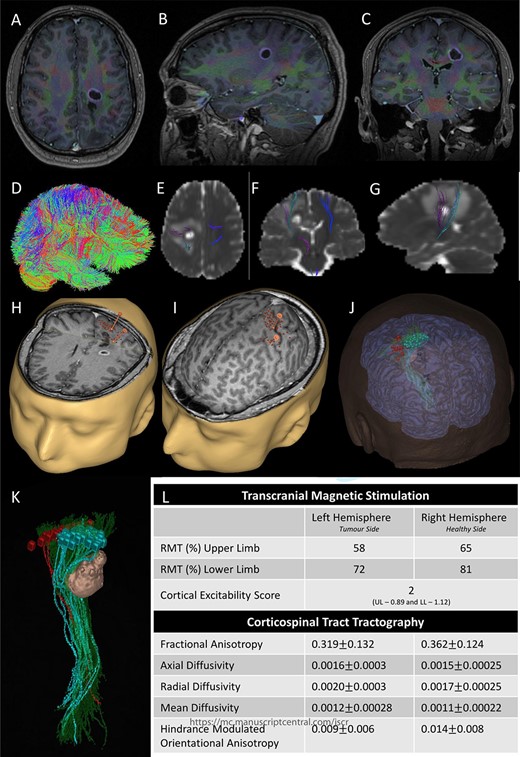

(A) Axial T1-weighted image with gadolinium showing the lesion with imposed DTI tractography of the CST; (B) planned trajectory for insertion of the tubular retractor guided by the preoperative integrated anatomical and functional motor mapping.

5-Aminolevulinic Acid (5-ALA) was given orally 2 h before the surgery. The least disruptive trajectory was selected taking into account the previous biopsy and the preoperative mapping information (Fig. 3). Under Stealth guidance, a skin incision was made overlying the planned craniotomy site. After the craniotomy, the dura was opened and a subdural strip of electrodes was placed over the primary motor cortex. Replicable motor responses from the hand muscles were obtained at 7 mA current intensity (Fig. 4). Motor evoked potentials (MEPs) were obtained continuously throughout the procedure. A transsulcal parafascicular approach was used. The sulcus was opened sharply under the microscope. At the depth of the sulcus, a preselected tubular retractor (NICO BrainPath 75 mm × 13 mm) was passed to the superficial surface of the lesion. While performing brain cannulation to the lesion, a monopolar probe (INOMED©) navigated with SureTrack (MEDTRONIC©) was used to perform continuous subcortical stimulation, train-of-five technique using high-frequency stimulation.